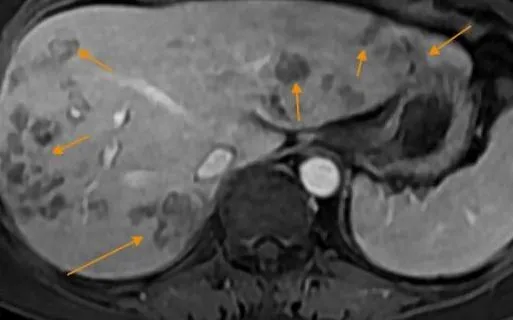

Chụp cộng hưởng từ (MRI) ổ bụng phát hiện nhiều ổ tổn thương khu trú gan phải, nghi do ký sinh trùng. Xét nghiệm chuyên sâu xác nhận bệnh nhân dương tính với sán lá gan lớn và giun lươn. Anh N. được chẩn đoán tổn thương gan do sán lá gan lớn kèm rối loạn lipid máu, bác sĩ kê phác đồ điều trị và hẹn tái khám sau 1 tháng.